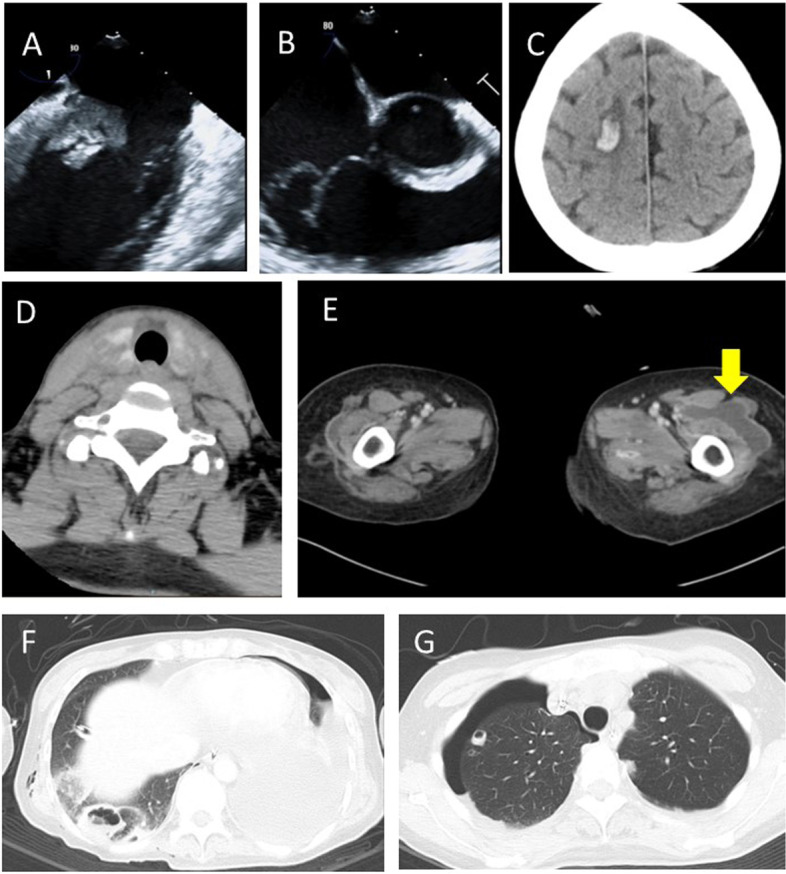

Transthoracic echocardiography showed that left ventricular wall motion was generally reduced, and its ejection fraction was 25%. Transesophageal echocardiography revealed a 22 × 10 mm mobile mass on the posterior leaflet of the mitral valve (Fig. 1A) and mild mitral regurgitation. There was also a mobile mass on the posterior leaflet and the chordae tendineae of the tricuspid valve (Fig. 1B), and tricuspid regurgitation was moderate. Brain computed tomography (CT) scan revealed hemorrhagic cerebral infarction (Fig. 1C, Fig. 2A). Contrast-enhanced CT confirmed bilateral thyroiditis (Fig. 1D); abscess formation in the left thigh (Fig. 1E), right thigh, right shoulder joints, and right lung (Fig. 1F); and secondary pneumothorax in the right lung (Fig. 1G).

Fig. 1.

A 22 × 10 mm mobile mass on the posterior leaflet of the mitral valve (transesophageal echocardiography [TEE]). B Mobile mass on the posterior leaflet and the chordae tendineae of the tricuspid valve (TEE). C Hemorrhagic cerebral infarction (Brain computed tomography [CT]). D Bilateral thyroiditis (contrast-enhanced CT). E Abscess in the left thigh (contrast-enhanced CT). F Abscess in the right lung (chest CT). G Secondary pneumothorax in the right lung (chest CT)